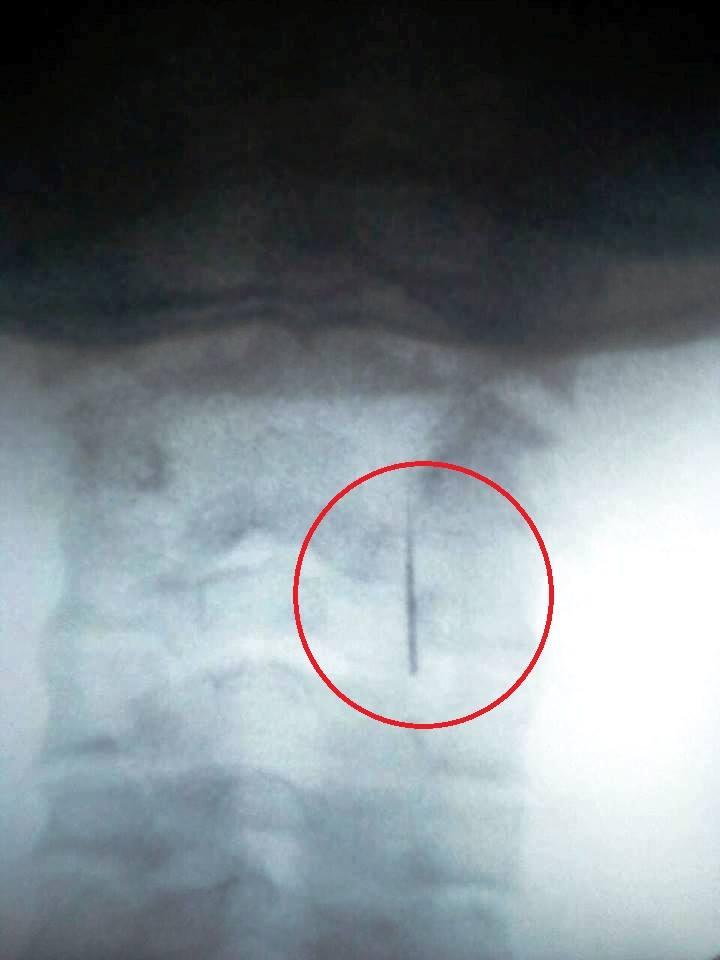

Після біганини з бідолашною дитиною лікарнями Ужгорода (стоматологічна поліклініка - дитяча поліклініка - Чоп - райлікарня - райлікарня в Ужгороді - міська поліклініка на БАМі) протягом двох днів таки виявили причину наростаючого болю в горлі дитини. Лікар-рентгенолог виявив сторонній предмет у горлі хлопчика, " виписав перший змістовний медичний документ і видав його мамі, - пише Лора Приходько. - І негайно послав до хирурга в обласну лікарню. ... Лікарі одразу приступили до роботи. Голку нарешті, якось витягли! Казали, що вона могла б попасти в трахею, в легені і тоді б..."

Зрештою, усе закінчилося щасливо, але питання залишилися... Питння до лікаря, "який витягуючи нерв із зуба, загубив у дитині в горлі голку, з намотаним на неї нервом і навіть не помітив цього? А, потім, на наступний день, відмовився оглянути дитину і з"ясувати що в нього за проблеми".